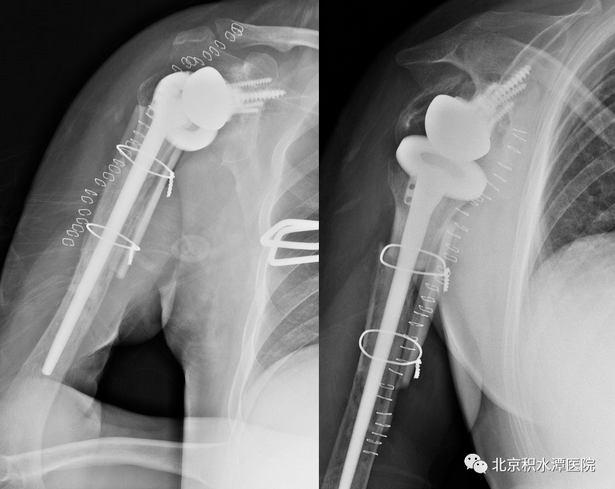

术后患者复查CT,见肩胛盂骨性重建良好。但为解决现有假体长度不足的问题,此次术后,蒋协远教授、黄强主任医师就带领团队医生与工程师团队进行了反复沟通,开始设计并定制合适的反肩假体。按健侧长度计算,肱骨近端骨缺损约8厘米,起初还在肿瘤型假体和APC方式间反复讨论,最后决定采用定制反肩假体结合异体骨(APC)的方式进行处理,同时还定制了相应长度的异体骨,以更好地恢复上肢长度和三角肌张力。

患者再次回到北京积水潭医院,蒋协远教授带领黄强主任医师和查晔军副主任医师、公茂琪主任医师等为患者进行了APC反肩置换手术治疗。术中见肩胛盂骨性结构重建良好,取出螺钉,顺利安装肩盂侧反球假体。并反复通过测量和软组织张力判断,确定了异体骨长度,安装肱骨侧假体后,以异体骨板捆扎保护,手术过程顺利,拍片见肩关节假体位置满意。